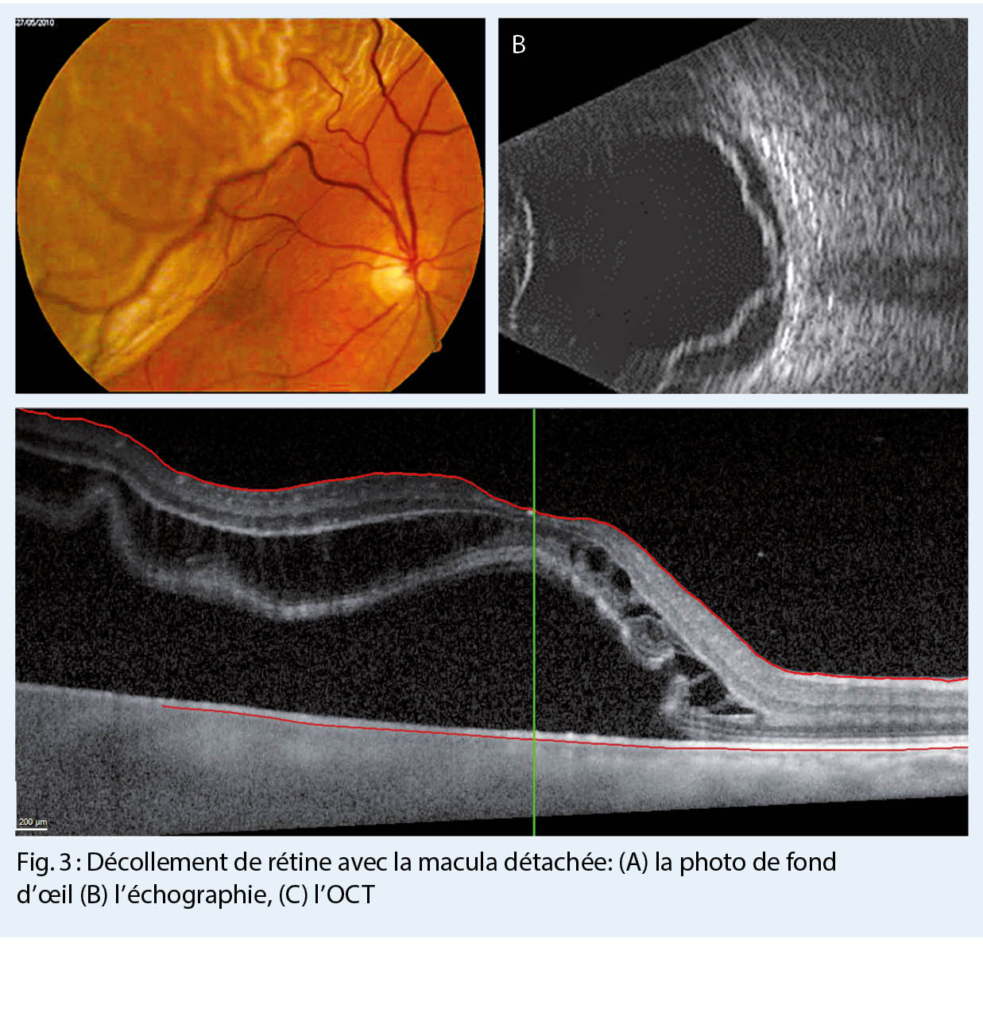

Le diagnostic du DR est basé sur l’ examen ophtalmologique avec les pupilles dilatées et sur une bonne anamnèse (1-4), i.e. la position du voile dans le champ visuel correspond à la partie de la rétine surélevée, qui est « inversée » dans l’ œil (la figure 2b montre le voile en inférieur qui correspond à un DR supérieur). L’ examen standard comprend : l’ acuité visuelle, la pression intraoculaire, l’ examen de la partie antérieure de l’ œil à la lampe à fente et ensuite l’ examen du vitré et du fond d’ œil avec les pupilles dilatées. Dans le vitré, on peut observer de la « poussière de tabac », c’ est-à-dire de petites parties de l’ épithélium pigmentaire rétinien déchirées (1, 3). Le diagnostic définitif est posé par ophtalmoscopie indirecte, lorsque la rétine décollée avec une ou plusieurs déchirures peut être observée (fig. 3A). Dans le cas où la déchirure de la rétine a aussi déchiré un vaisseau sanguin de la rétine, il y a une hémorragie vitréenne, qui empêche l’ophtalmoscopie indirecte. Dans ce cas, le diagnostic définitif est posé par l’ échographie (fig. 3B). Dans les plus grands hôpitaux, bien équipés, une imagerie de la rétine est faite aussi en supplément (OCT = la tomographie en cohérence optique), qui donne des informations microscopiques précises des changements dans les couches rétiniennes (fig. 3C) (1, 3). Ces informations peuvent aider pour estimer la récupération fonctionnelle.

Le degré de la récupération fonctionnelle a été associé à la durée du DR, au degré de myopie, à l’ âge et à la persistance du liquide sous-rétinien (5). La sensibilité visuelle est directement liée à la densité des photorécepteurs (cellules hautement spécialisées pour la vision) dans la rétine. La zone la plus dense des photorécepteurs est la macula, responsable de la vision centrale (c’ est-à-dire de la lecture). Étant donné que la mort des photorécepteurs commence dans les douze premières heures et culmine à 2-3 jours après le DR, il est important d’ effectuer une chirurgie le plus rapidement possible (6, 7, 8).